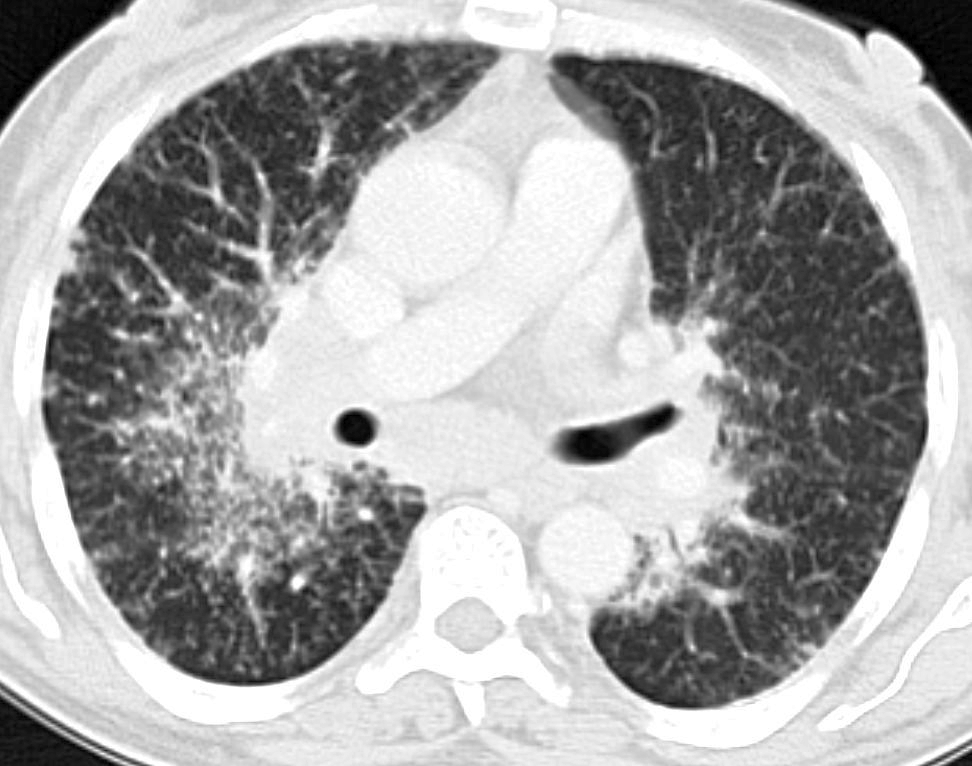

Визуализация и диагностика неинвазивного аспергиллеза с помощью КТ

Раздел: Необычные решения